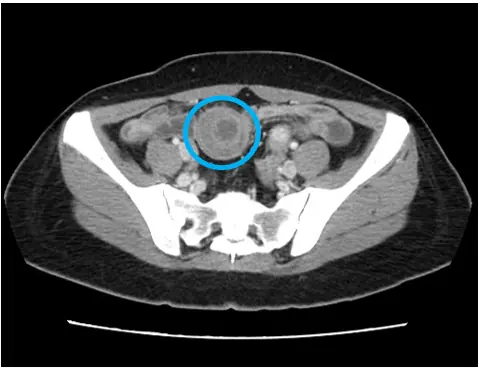

收治該患者的腸胃科黃一修醫師表示,患者的腹痛並非一般胃炎,經安排腹部電腦斷層檢查,影像顯示小腸出現「標靶徵象」,診斷為「腸套疊」。立即啟動跨科會診,將患者轉由一般外科王志浩醫師接手,進行緊急微創手術治療。

圖二:小腸套疊腹部電腦斷層影像(圈圈處)。